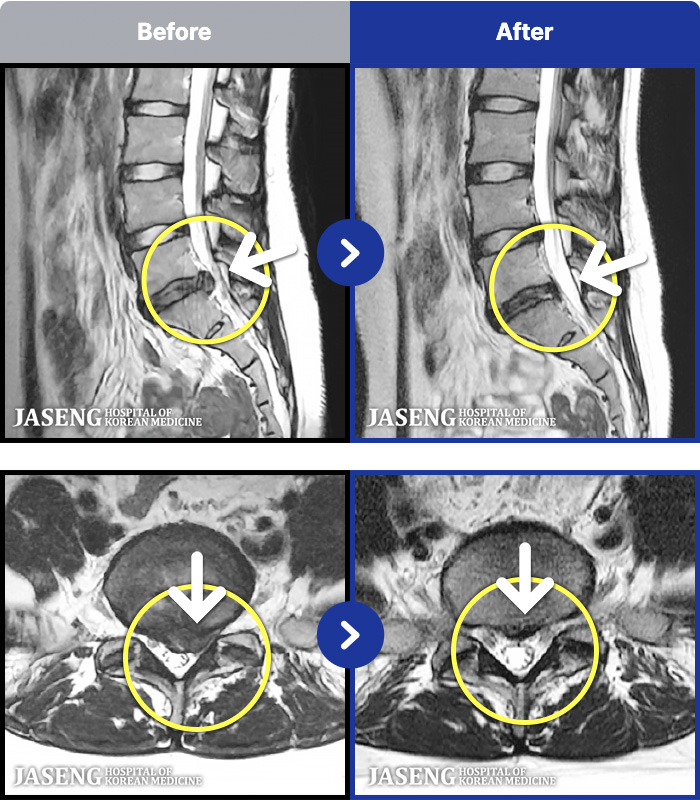

1,291 MRI ũ ʸ Ȯϼ.

[뱸] 19.11.28~25.05.06